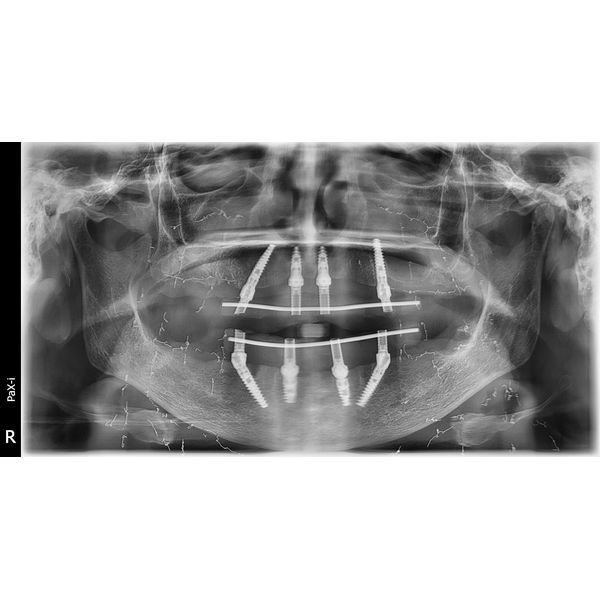

- одномоментно установили импланты в область ранее удалённых зубов на обеих челюстях;

- зафиксировали на имплантах мультиюниты, которые позволят прикрепить протезы с помощью винтов;

- сняли слепки с обеих челюстей для изготовления временного несъёмного зубного протеза на винтовой фиксации.

Полгода женщина носила временную конструкцию. За это время она дважды делала контрольные ортопантомографические снимки и компьютерную томографию, чтобы контролировать состояние полости рта. Когда импланты прижились, ей поставили постоянный протез.